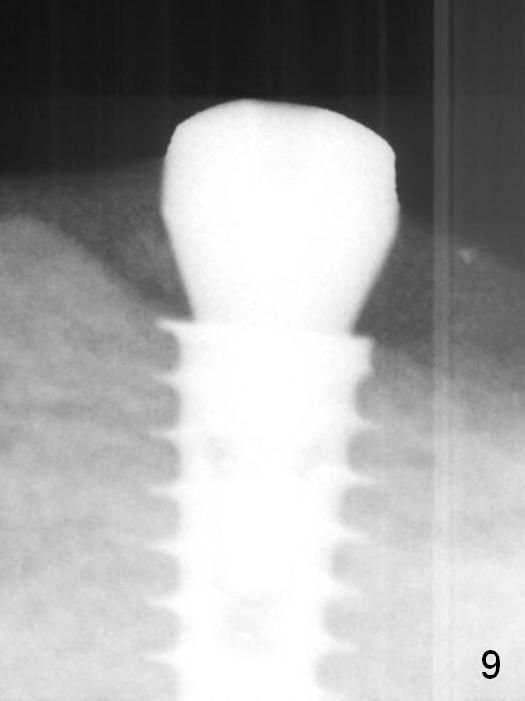

A 5x9 mm implant is placed with a pair abutment (A) to test the trajectory (Fig.6). The implant appears to have osteointegrated 2 months postop (Fig.9 with a healing abutment). There is no bone resorption 1 year 4 months post cementation (Fig.16). The implant remains stable 3.5 years post cementation (in spite of open margin), while the other abutment for the RPD (the tooth #30) has mobility with gingival recession.